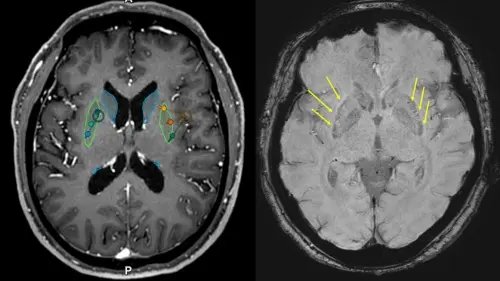

이식 전(왼쪽) 후(오른쪽) MRI, 이식 후 MRI에서 성공적으로 세포가 이식된 부위를 확인할 수 있다(화살표)